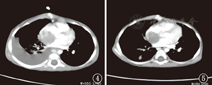

本研究中伴下腔静脉瘤栓10例,占19.23%(10/52例),其中2例经下降静脉血行播散至右心房形成巨大转移瘤。2例均为男童,初诊年龄分别为3岁1个月和3岁10个月(图4、图5)。3岁1个月患儿肺转移出现于介入治疗及右心房瘤栓切除术后,经术后化疗后达到部分缓解11个月,后因心脏转移瘤、肺转移、肝内多发转移复发后经化疗7个周期病情进展死亡,OS为2年11个月。3岁10个月患儿,病初经术前全身化疗4个周期、手术治疗、术后化疗9个周期达到完全缓解,截止随访日期无病生存21个月。

与治疗相关的影响预后的因素有远处组织器官转移,中心静脉、腔静脉侵犯,尾状叶侵犯以及肝内多发占位[12]。本研究中,以肺转移以及下腔静脉侵犯最为多见,由于肝脏血流丰富可沿下降静脉、肝门静脉血行播散至肺循环而形成肺转移瘤,可为单侧肺或双侧肺多发转移。值得注意的是,本研究中2例出现右心房巨大占位,分析病情均因下腔静脉瘤栓蔓延所致,但由于心脏血流量大、流速快形成占位仍较为罕见。观察2例患儿的诊疗经过,术前全身化疗达到完全手术切除非常重要,而介入治疗、心房转移灶手术风险较大且易复发。虽然本研究中心房转移病例较少,但从诊疗经验分析,介入治疗及早期心脏转移瘤手术应慎重进行。同时,对于上腹部CT提示怀疑下腔静脉瘤栓患儿应行血管超声、心脏超声检查。另外,本研究中31例出现复发(59.61%),2年EFS仅为22.58%,而3、5年的OS仅为32.69%、15.38%。复发严重影响预后。所以,如何降低Ⅳ期HB复发对于最终提高生存率至关重要。而目前国内方法不多,今后应在新药物的使用、生物治疗、免疫治疗等方面进行研究及观察,从而找到Ⅳ期HB复发病例最佳的综合治疗方法。